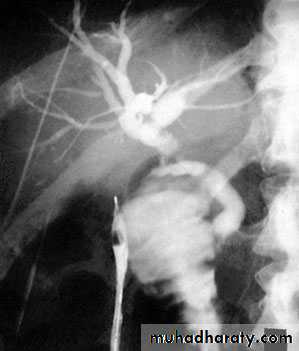

For proximal tumours, percutaneous transhepatic cholangiography is the most useful modality.

PTC

outlines the anatomy of the tumour and the intrahepatic biliary system.

it allows percutaneous biliary drainage,

samples can be obtained for cytology

to confirm the diagnosis.

Transhepatic cholangiogram showing a stricture of thecommon hepatic duct